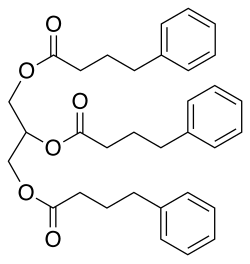

- Glycerol phenylbutyrate